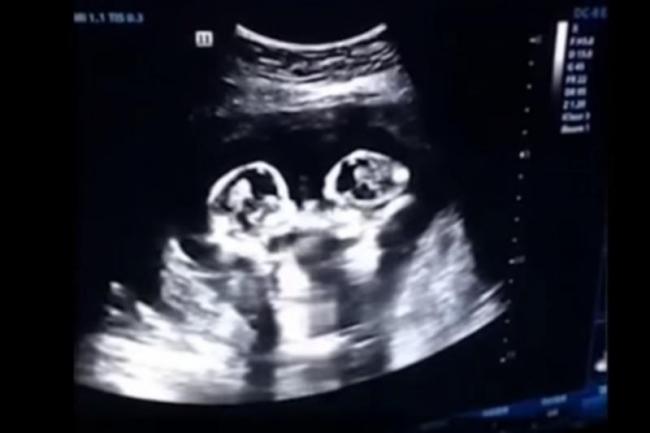

తోడపుట్టిన అక్కాచెల్లెళ్లు, అన్నాతమ్ముళ్ళు కొట్టుకోవడం చూశాం. అది బయట. కానీ ఈ వీడియో చూస్తే ఇదేమి అద్భుతమూ అని అనిపించకమానదు. సహజంగా కవలపిల్లలు కొట్టుకోవడం చూసుంటారు.. కానీ తల్లిగర్భంలోనే చేతులతో కిక్బాక్సింగ్ ఆదుకోవడం ఎక్కడా చూసి ఉండరు. చైనాలో అదే జరిగింది. అందుకు రుజువు ఈ వీడియోనే పిండాల దెబ్బలాటకు సంబంధించిన వీడియో తెగ వైరలవుతోంది. చైనాకు చెందిన ఓ మహిళ నాలుగో నెలల గర్భంతో ఉండగా వైద్య పరీక్షల నిమిత్తం ఆస్పత్రికి వెళ్లింది. అక్కడ వైద్యులు ఆమెకు అల్ట్రాసౌండ్ స్కానింగ్ చేశారు.

ఈ సమయంలో తల్లి గర్భంలో ఉన్న ఇద్దరు కవలలు ఒకరితో ఒకరు పోట్లాడుకుంటూ కనబడ్డారు. అంతే స్కానింగ్ వైపు చూసిన ఆ మహిళ భర్త షాక్ కు గురయ్యాడు. ఇదేమి అద్భుతం అనుకుంటూ.. ఈ దృశ్యాన్ని తన ఫోన్ లో రికార్డు చేశాడు. అది డాక్టర్లకు చూపించడంతో వారు తమకిందంతా మామూలే అనుకుని వదిలేశారు. అయితే ఈ వీడియో అతను సామాజిక మాధ్యమాల్లో షేర్ చేశాడు. అంతే అది కాస్త వైరల్ గా మారింది.ఈ వీడియో చూసిన నెటిజెన్లు వీరు ఖచ్చితంగా బాక్సర్లే అవుతారు అని కామెంట్లు చేస్తున్నారు. ఓసారి మీరు కూడా ఓ లుక్కేయండి.